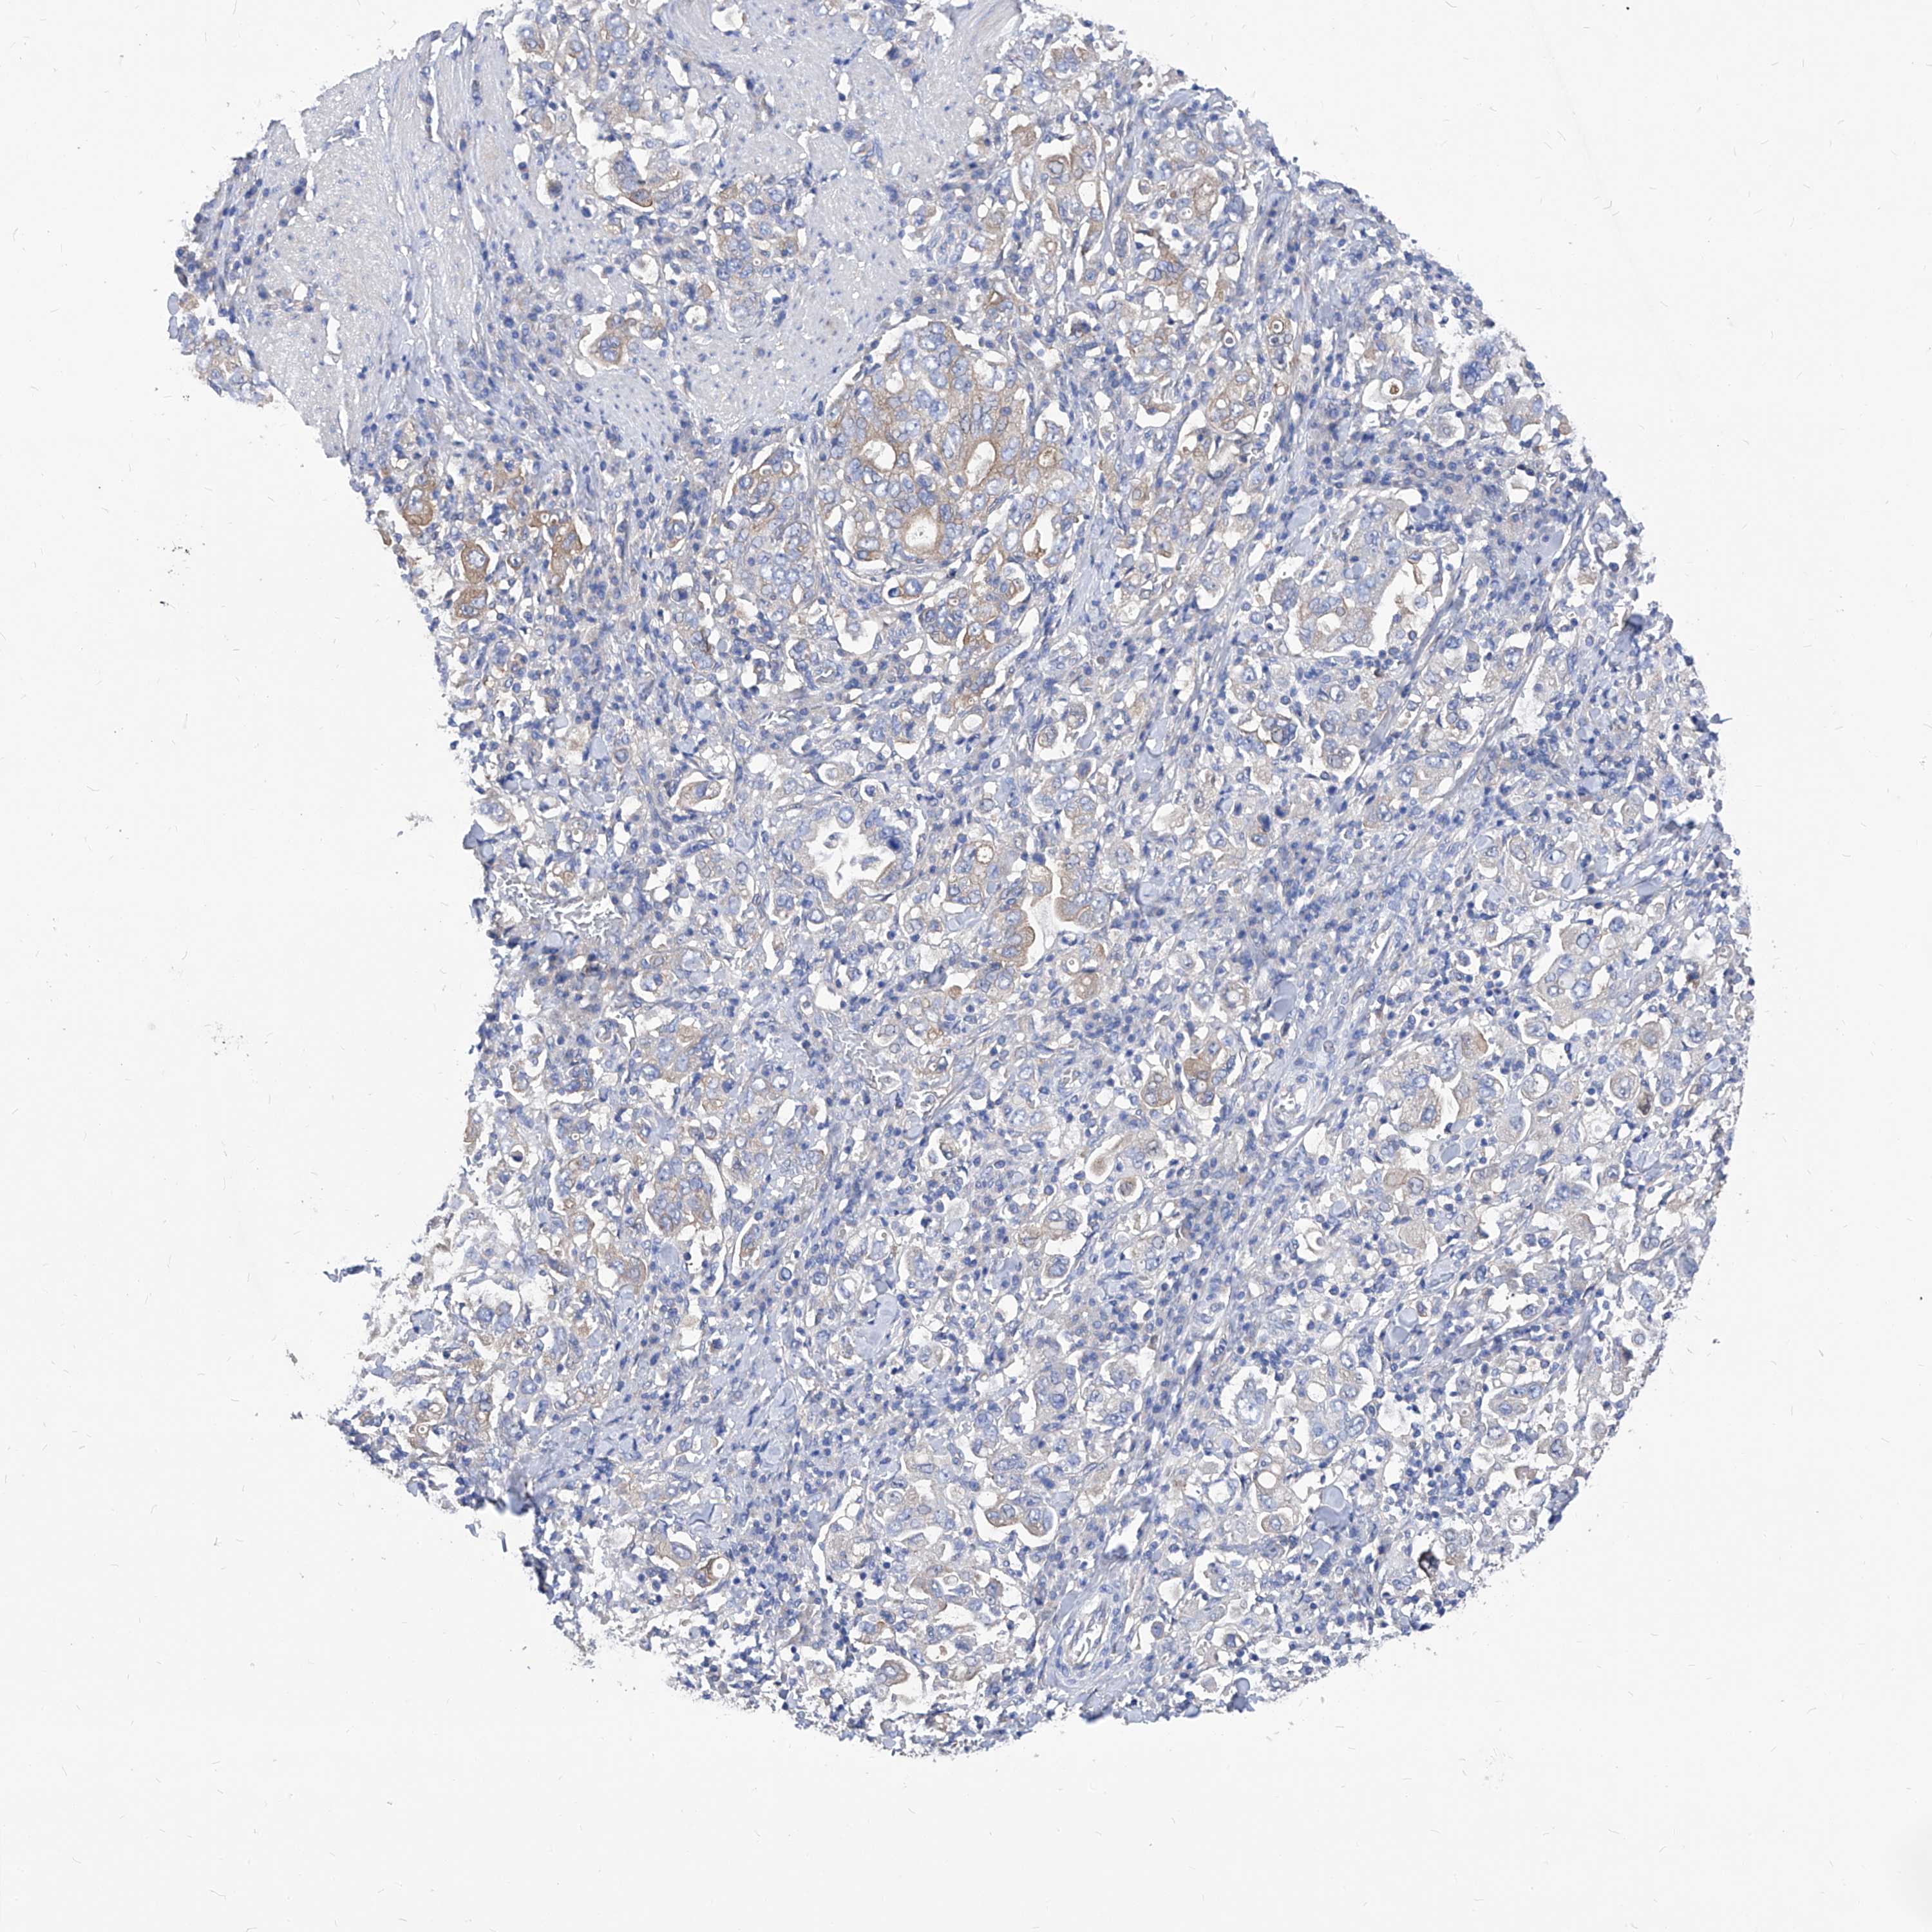

STOMACH CANCER - Protein expressioni

A mouse-over function shows sample information and annotation data. Click on an image to view it in a full screen mode. Samples can be filtered based on level of antibody staining by selecting one or several of the following categories: high, medium, low and not detected. The assay and annotation is described here.

Note that samples used for immunohistochemistry by the Human Protein Atlas do not correspond to samples in the TCGA dataset.

Antibody stainingi

Antibody staining in the annotated cell types in the current human tissue is reported as not detected, low, medium, or high, based on conventional immunohistochemistry profiling in selected tissues. This score is based on the combination of the staining intensity and fraction of stained cells.

Each image is clickable and will lead to virtual microscopy that enables deeper exploration of all samples and also displays staining intensity scores, fraction scores and subcellular localization as well as patient and tissue information for each sample.

HPA030419

HPA030420

HPA030422

CAB025196

CAB080286

CAB080287

Staining

High

Medium

Low

Not detected

Intensity

Strong

Moderate

Weak

Negative

Quantity

>75%

75%-25%

<25%

None

Location

Nuclear

Cytoplasmic/membranous

Cytoplasmic/membranous,nuclear

Adenocarcinoma, NOS

Adenocarcinoma, High grade